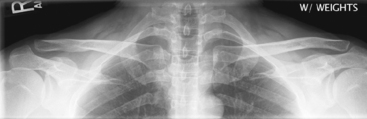

(AP—Bilateral with and without Weights)

Warning: Rule out fracture first before taking “with weight” projection.

• 35 × 43 cm C.W. (14 × 17″) or (2) 18 × 24 cm (8 × 10″) for broad shoulders